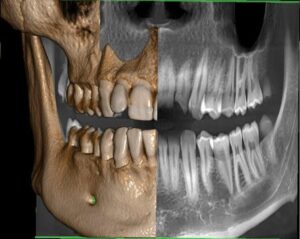

Fotografimi i dhëmbeve- Ortopani

- Rëntgeni Ortopan, mundëson identifikimin mjaftë të suksesshëm të dhëmbëve, të nofullës së poshtme dhe të sipërme, si dhe formacionet patologjike të kockave të nofullës.

- Karakteristika më e rëndësishme është zbulimi i të gjitha detajeve që janë të pamundur të vërehen përmes shikimit me sy si dhe kontribojnë në diagnostikimin dhe trajtimin e saktë nga mjeku.

- Për këtë arsye pas ekzaminimit të parë të pacinetit sipas kërkesave shërben si një prej metodave më të kërkuar në drejtim të përcaktimit të trajtimit.